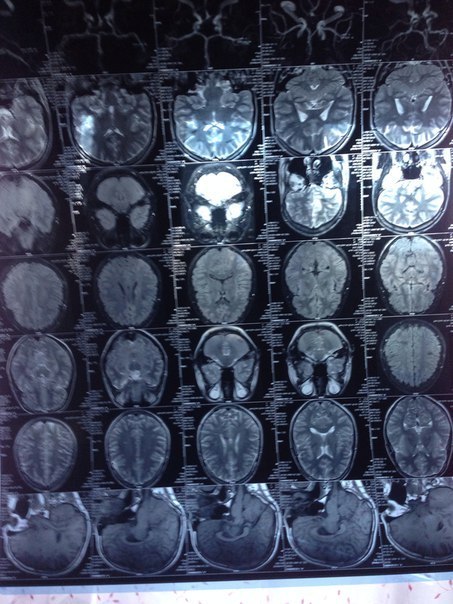

Может все таки ЭЭГ?